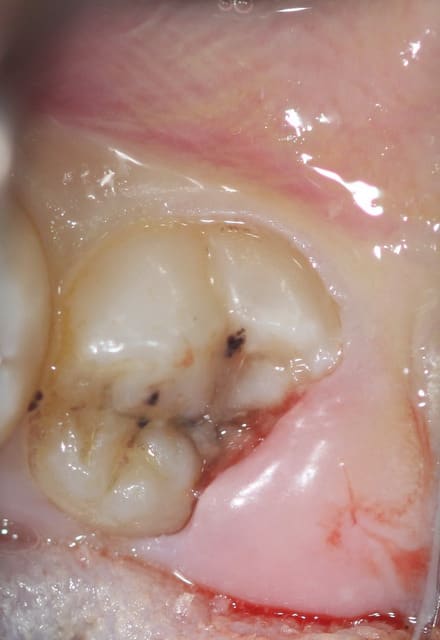

jeune patiente de 18ans avec sa 38completement dégagée de l'os mais persistance d'un capuchon muqueux régulièrement inflammatoire et douloureux... pour conserver la dent... que faire? un distal-wadge (pas sur de l'orthographe) une suppression du capuchon distal... j'en ai jamais fait... dois je procéder comme pour une élongation coronaire? ou incision en quartier d'orange???

cela dit, vu les débuts d'attaques carieuses sur cette dent, je pense que ton patient ne finira pas sa vie avec cette 8. J'opterais probablement pour son élimination.

voila finalement on a opter pour la conservation de la dent...

Décapuchonné à la lame froide saignement modéré (infiltration d’anesthésie adrénalinée tout autours de la couronne... Un point de suture dix jours après compo. conseils d’hygiène.

la patiente est contente d'avoir conserver sa dent...